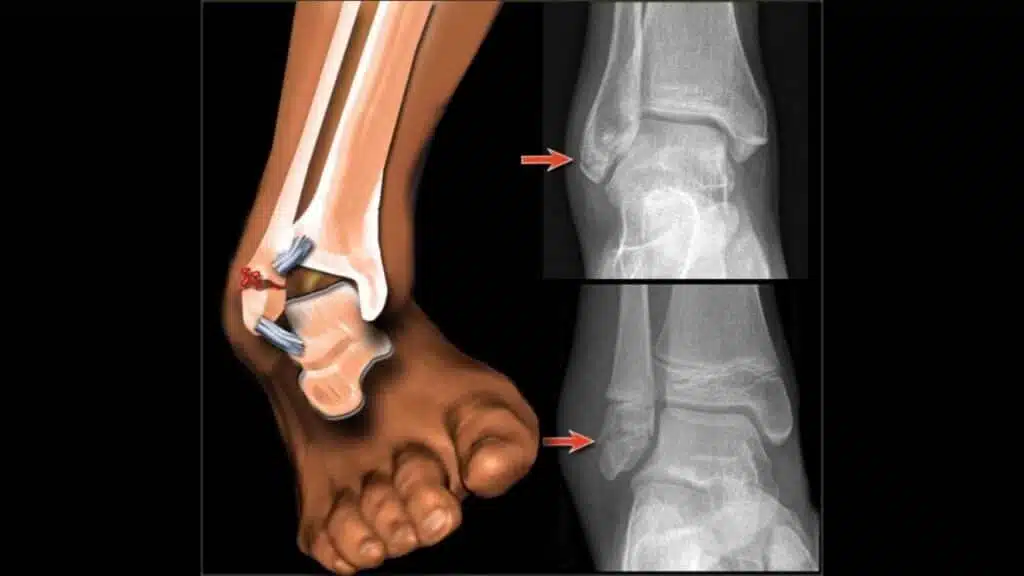

يوجد أكثر من نوع للعمليات الجراحية التي يتم استخدامها لعلاج الكسور منها تركيب الشرائح والمسامير وهي من الإجراءات الطبية الحديثة نسبيا والتي تعمل على تثبيت وتدعيم العظم المكسور.

عملية تركيب شريحة ومسامير في الساق

يعمل الجراح أثناء عملية تركيب الشريحة والمسامير على أن يثبت العظام جيدا لكي تقدر العظام على الالتئام مرة أخرى ويقدر المصاب على استعادة النشاط البدني الطبيعي له، ويوجد أكثر من نوع من المسامير والشرائح منها النيكل والكوبالت وغيرها ويختار الطبيب المعالج النوع الأنسب لإجراء العملية.

يتم إجراء مثل هذا النوع من العمليات تحد تأثير التخدير الكلي لأنها من العمليات التي تستغرق بعض الوقت للقيام بها، وفي الغالب لا تخرج الشرائح والمسامير من الجسم لأنها مصممة لكي تكون صالحة للتواجد في العظام المصابة مدى الحياة، ولكن إذا حدث منها مضاعفات أو ألم وتورم يزاد بمرور الوقت في العظم المصاب يمكن أن يزيلها الطبيب بعد حوالي عام من الجراحة.